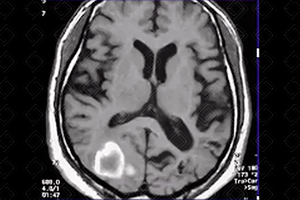

Texto alternativo para a imagem Figura 3. Créditos: Dra. Elazir Mota - Rio de Janeiro/RJ

Descrição das figuras 3, 4 e 5: Ressonância magnética do crânio (esquerda para a direita: T2/difusão/T1): presença de hematoma occipital direito, paciente normotenso – provável angiopatia amiloide.

• Angiopatia amiloide: Hemorragia lobar espontânea, idosos normotensos e com demência. Caracteristicamente, as áreas de sangramento se apresentam como focos múltiplos que poupam os núcleos da base e o tronco cerebral e estão localizadas na junção corticomedular (f iguras 3, 4 e 5);